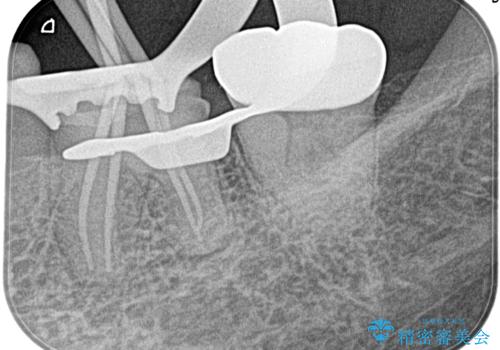

奥歯がズキズキ痛い 根管治療

- 冷たいもので強い痛みがあり、1週間前ぐらいからズキズキ痛いことを主訴に来院されました。

患歯に冷温刺激に対し20秒の持続痛と打診を認めたため、不可逆性歯髄炎の診断とし治療を行なっております。

不可逆性歯髄炎と診断される場合は、経過観察を行なっても正常歯髄に戻る可能性は極めて低いため今回の処置のように抜髄の適応となります。